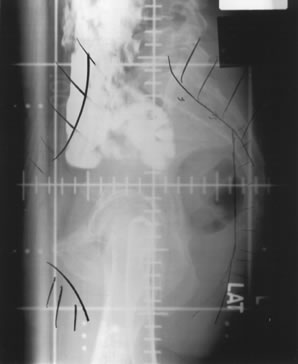

Whole-pelvic irradiation can be accomplished by either a two-field or four-field technique. To avoid excessive maximal dosages, the two-field technique should be used only with high-energy beams. The two-field technique uses opposed anterior and posterior fields (Fig. 1). The upper border of the field is generally placed at the L4-5 or L5-S1 interspace. If there is no disease extension into the vagina, the lower border should encompass one half to two thirds of the vagina. The lateral borders should be placed approximately 1.5 cm lateral to the bony pelvic rim. A marker should always be placed to indicate the location of the vaginal cuff/cervix or the most distal aspect of tumor extension. The four-field technique allows lateral shielding of structures that cannot be shielded in the anteroposterior field. This is my preferred method of pelvic irradiation. In the four-field technique, the upper and lower field borders are identical to those in the two-field technique. The anterior border of the lateral field is placed at or anterior to the anterior pubic symphysis. The posterior border is placed at the S2-3 interspace unless tumor extension necessitates larger fields. An example of a lateral field is shown in Figure 2.

Fig. 1. Simulation radiograph of an anteroposterior whole-pelvic radiation field.